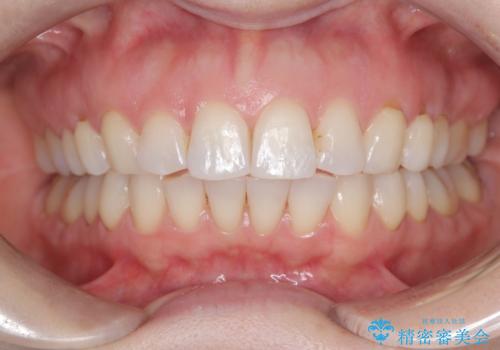

審美装置を用いたワイヤー矯正|非抜歯で歯の凸凹を改善

- 患者様は**歯の凸凹(叢生)**を気にされて来院されました。診査の結果、歯列のスペースが不足しているものの、抜歯をせずに改善できる状態でした。そこで、目立ちにくい審美装置(白いブラケットとホワイトワイヤー)を使用したワイヤー矯正を提案しました。歯列のアーチを広げながら、適宜IPR(歯の幅をわずかに調整する処置)を行い、非抜歯で自然な歯並びへと導く計画を立てました。

治療では、白いブラケットとホワイトワイヤーを使用し、矯正装置が目立ちにくいよう配慮しました。歯列を拡大しながら適切に歯を移動させ、IPRを併用することで、無理なくスペースを確保しました。見た目に配慮しながら、歯の凸凹をスムーズに整え、噛み合わせも改善。患者様からは「装置が思ったより目立たず、歯並びがきれいになって嬉しい」との声をいただきました。